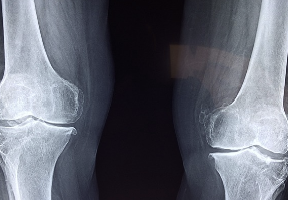

1. 관절염 예방 및 치료

콘드로이친은 관절염의 원인 중 하나인 연골의 손상을 방지하고 복구하는데 도움이 됩니다. 연구에 따르면, 콘드로이친을 복용한 환자들은 연골의 두께와 밀도가 증가하고, 관절염의 증상이 개선되었다고 보고했습니다. 콘드로이친은 특히 무릎 관절염에 효과적인 것으로 알려져 있습니다.